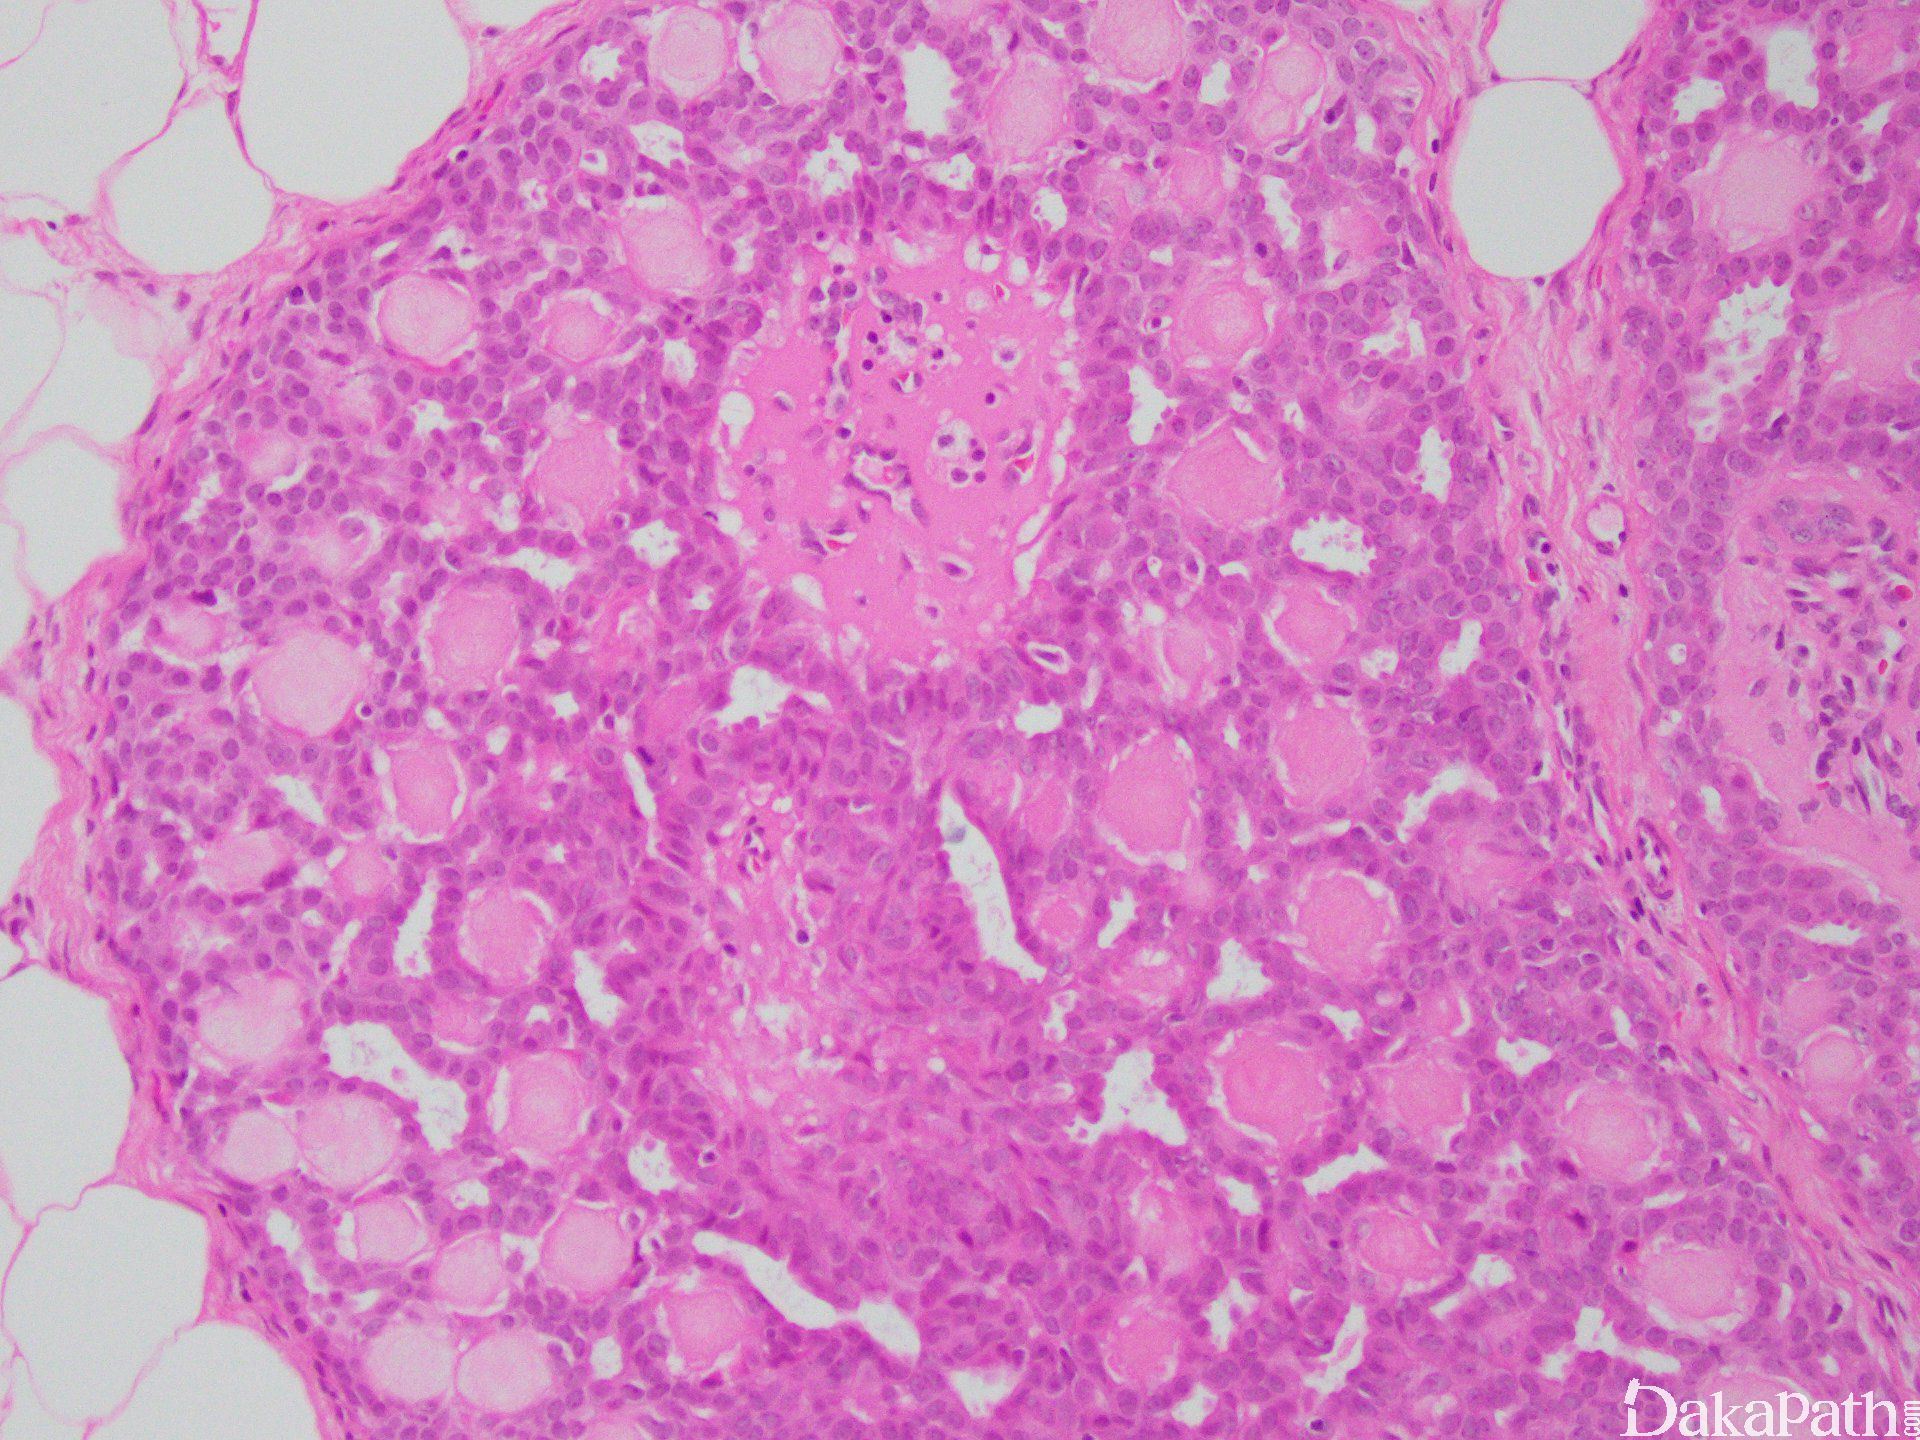

- 低倍镜显示界限清楚的导管内或囊内乳头状增生结节;

- 乳头纤维血管轴心覆以两种细胞,排列于乳头状结构面向管腔面的上皮细胞和位于上皮细胞和基底膜之间的肌上皮细胞;

- 上皮细胞可为一层或多层,立方形或柱状。肌上皮细胞立方或长轴平行于基底膜的短梭形,胞浆透亮,也可以增生,呈多层;

- 上皮细胞增生明显时,相邻乳头之间的上皮细胞相互连接,低倍镜下乳头结构模糊不清,但高倍镜下可见纤维血管轴心;

- 上皮细胞增生区域细胞呈流水样或螺旋状分布,胞质边界可形成不规则缝隙,这些特征均提示良性增生;